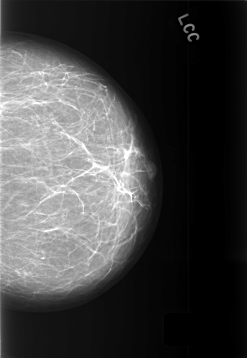

C_0446_1.LEFT_CC

LEFT_CC LINES 5720 PIXELS_PER_LINE 3944 BITS_PER_PIXEL 12 RESOLUTION 50 NON_OVERLAY